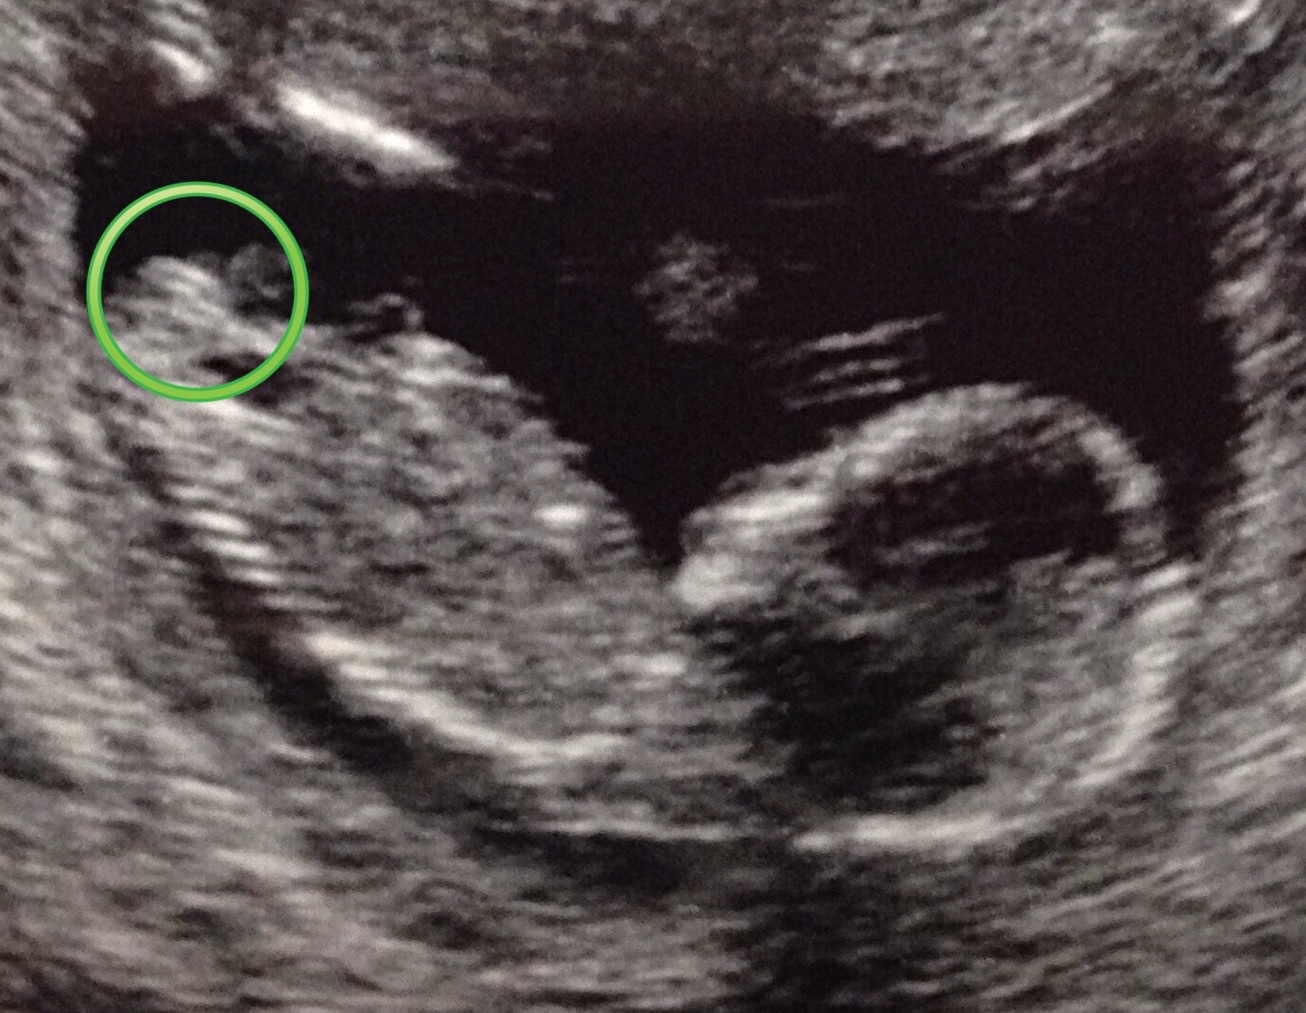

Attachment 23616Would love some opinions on this 14w nub!

I really hope so!! At 14 weeks it's probably not going to spawn a bump and go up right?

You've got cord in the way hard to tell which is the top. Because if it's the top few lines That would be boy.

Thanks! Are you talking about the shadow in the back? Cause I was thinking that was the thigh. The shin of the lower leg is the floating line above and the foot is pushed up against a the uterine wall. (Got some super cute pics of feet!) I only ask just cause you're the first person to say boy and cord :)

Nope you are totally right on your labeling. The cord is in purple which runs behind and in between the legs where the mess of a gender is LOL It also looks from the "scratch marks" up by the head (hand movement) youve got quite the mover and baby is just about to roll so that really flubs up the angle. Im more inclined to go with girl because of the way it looks but just cant be sure because of the rotation plus cord. Depending on the movement either the part in pink is correct and girl or the part in blue is correct and boy. All that cord and movement this one is already trouble from the start HAHA! Attachment 23638